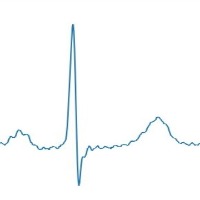

Couplet Computer Vision Project

Cardiac Monitoring: Couplet can be incorporated into patient monitoring systems to detect the various types of couplets in real-time, allowing healthcare professionals to identify arrhythmias and other cardiac anomalies. Early intervention can lead to better patient outcomes.

Telemedicine: Couplet can be integrated into telemedicine platforms to remotely assess a patient's electrocardiogram (ECG) signals. This helps improve access to care for patients who live in rural or hard-to-reach areas, allowing physicians to review their ECG and determine if there are any issues that require immediate attention.

Wearable Device Analysis: Couplet can be embedded into wearable health devices, such as smartwatches or fitness trackers, to analyze ECG data in real-time. This can help users monitor their heart health and alert them to any abnormalities, encouraging proactive healthcare management.

Medical Research: Couplet can be used by researchers studying the prevalence and causes of various couplet types. Automating the identification process can save time and improve accuracy, allowing researchers to focus on understanding the underlying mechanisms and developing effective treatments.

Medical Training and Education: Couplet can be applied to educational materials and training modules, helping medical students and professionals learn to identify different couplet types. By automating the recognition process, trainees can test their skills and gain confidence in their ability to diagnose conditions related to couplet classes.